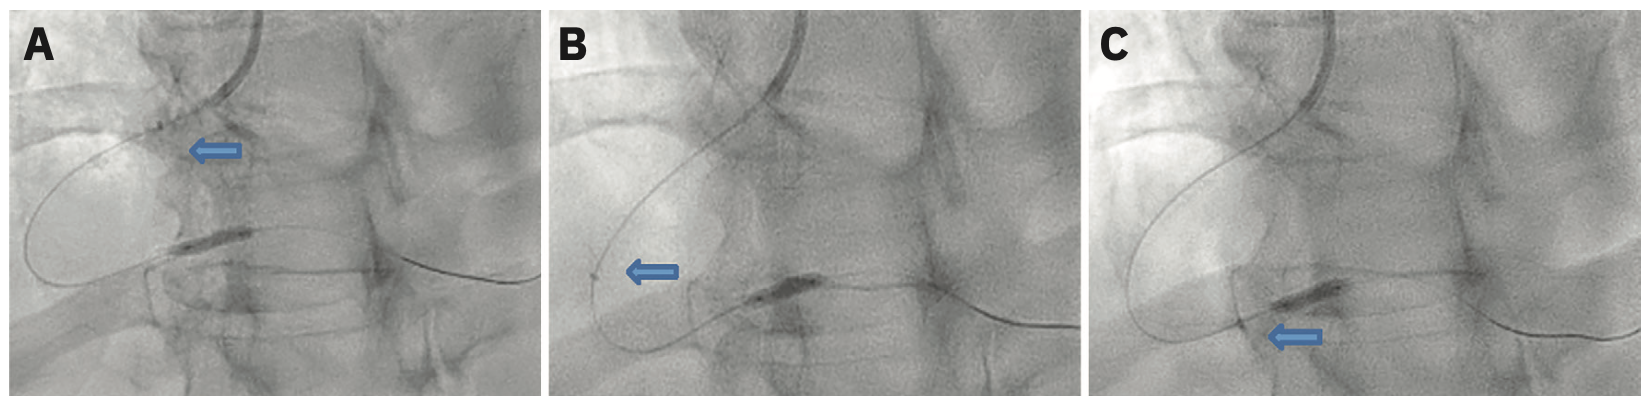

There are three different techniques that we use to deliver the guide catheter extension system. One is called the balloon surfing technique. The balloon surfing technique or balloon assisted tracking starts by deploying either a 2 or a 2.5 mm balloon at the tip of the catheter, with half sticking out of the catheter. The balloon is actually used as a bumper in an attempt to get past the lesion or to the lesion. A second technique called the balloon tracking technique or balloon anchor (Figure 1) is the most common technique I use. It entails inflating the balloon, whether a compliant or noncompliant balloon, at the distal vessel where the lesion is located, and while the balloon is up, tracking the guide catheter extension system to the lesion, to the balloon. It is almost like a balloon anchor. Whenever you are delivering the guide extension catheter system, it should always be done over a present balloon shaft or stent shaft. The reason is based on the old teaching that we should never go “bare,” meaning you should not push the guide extension catheter over a wire without any assisting balloon, because it can cause trauma to the vessel. The biggest complication that we see with guide extension catheters is dissection. Both the balloon surfing and the balloon tracking techniques allow for the presence of a stiffer shaft or a stiffer rail system for the guide extension catheter system to go over, thus limiting or preventing trauma to the vessel wall, and so these are the two main techniques we use to deliver the guide extension catheter system. Once the guide extension catheter system is at the balloon, there is also a technique called “inchworming” (Figure 2). After the balloon is inflated and as it is deflating, we push the guide extension catheter over the balloon. We will use the inchworming technique if there is significant proximal stenosis and we can’t get the guide extension past that stenosis to get to the lesion. We often will inflate a balloon at that proximal lesion, and as the balloon is coming down, push the guide extension catheter over the balloon, past the stenosis. A stent or an IVL balloon can then be delivered by unsheathing the guide extension catheter, because you are past the lesion. The use of these three techniques is crucial for IVL delivery in the treatment of calcified lesions. Without these techniques, delivering these devices becomes very difficult. Another problem is that when you are going through calcified and tortuous lesions, the balloon, the IVL catheter, and the stent can become damaged. The guide extension catheter actually protects devices from getting damaged. The biggest risk for IVL catheters is obviously balloon damage leading to a balloon rupture, which could then lead to dissection or damage to the arteries. Stents themselves can either be damaged and/or their drug coating can be damaged. Even worse is that the stent could be stripped off the balloon and you now have a freestanding stent in a vessel with calcified lesions. Guide extension catheter systems can prevent these complications from happening and it is absolutely crucial that interventionalists know how to use guide extension catheters.